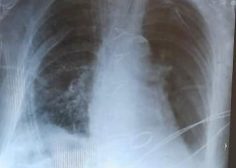

Severe Mitral stenosis and diaphragmatic hernia

90 years old female with RT sided diaphragmatic hernia and Severe Mitral stenosis undergone simultaneous repair with good course and post op xray.